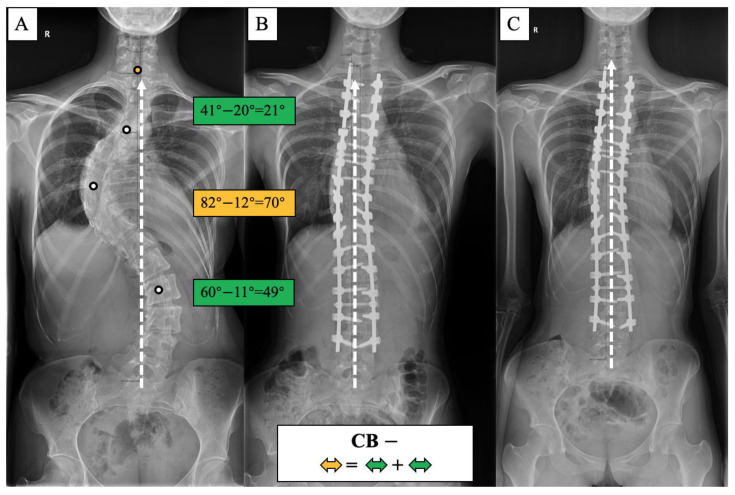

A surgical algorithm was proposed based on the CB classification to avoid postoperation CIB (Figure 3). In addition, a schematic diagram of the correction strategy for each type of patient is shown in Figure 4. For CB+ patients, the correction rate of the main curve (CRMC) should match the compensation curve. For CB− patients, the CRMC should match the compensatory curve. Most of the lumbar motion segments can be retained to provide optimal compensatory ability. However, the postoperative compensatory capacity of CB− patients is not as good as CB+ patients due to the limited mobility of the preserved lumbar motion segments. For CIB− patients, the CRMC should be greater than the compensatory curves. Osteotomy at the concave side of the main thoracolumbar curve is recommended. Multiple-level asymmetrical Ponte osteotomy is a safe and effective technique to improve the flexibility of the spine as well as the correction rate of rigid adult idiopathic scoliosis [ref. 15]. For CIB+ patients, the CRMC should be less than the compensatory curves, and the LIV should be kept even during the surgery. Preserving lumbar mobility is not the primary consideration when making a surgical plan for CIB+ patients. Typical cases are shown in Figure 5, Figure 6, Figure 7 and Figure 8.

The incidence of postoperative CIB was 50% in CB+ patients and 70% in CB− patients, which was the highest among the four groups. The majority of postoperative CIB in this case series was caused by a mismatch in the correction rate between the primary and compensation curves. Nearly half of the postoperative CIB was compensated to CB at the final follow-up, benefiting from the adjustment of the LIV inclination angle. The decompensation or CIB rate (CBD > 2cm) in the final follow-up was 28.26% and 40% in CB+ and CB− patients, respectively, higher than the 16.83% reported by Miller for 908 patients with AIS with a smaller preoperative Cobb angle of 60 degrees. To reduce the postoperative CIB, the correction rate of the main and compensatory curves should be consistent. Meanwhile, lumbar motion segments should be preserved as much as possible to provide the ability to spontaneously compensate. Bao et al. [ref. 22] reported that postoperative CIB with pelvic fixation may not compensate spontaneously during follow-up, resulting in permanent fixation decompensation.